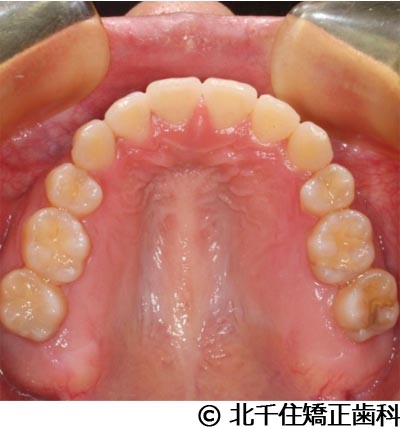

【症例3】叢生

- 治療前

- 治療後

- 治療名

- 叢生

- 費用

- 1,125,000円(税込)

- 期間

- 2年1ヵ月

- 治療回数

- 26回

- 通院頻度

- 1ヵ月ごと

- 年齢・性別

- 19歳3ヵ月・女性(初診時)

治療内容

-

患者様の症状

主訴:デコボコ、口元の突出

治療方法

上下顎第一小臼歯4本を抜歯してワイヤー矯正(セラミックブラケット)。

治療結果

叢生に対し抜歯を併用した矯正治療により、歯列および咬合関係の調整を行った症例である。治療後は保定装置を使用し、歯列および咬合の安定維持を目的として定期的な経過観察を行っている。

※治療結果は個人差があります。

治療を行う上での注意点(リスク・副作用)

歯磨き不良に伴うカリエスや歯周病、歯根吸収など。